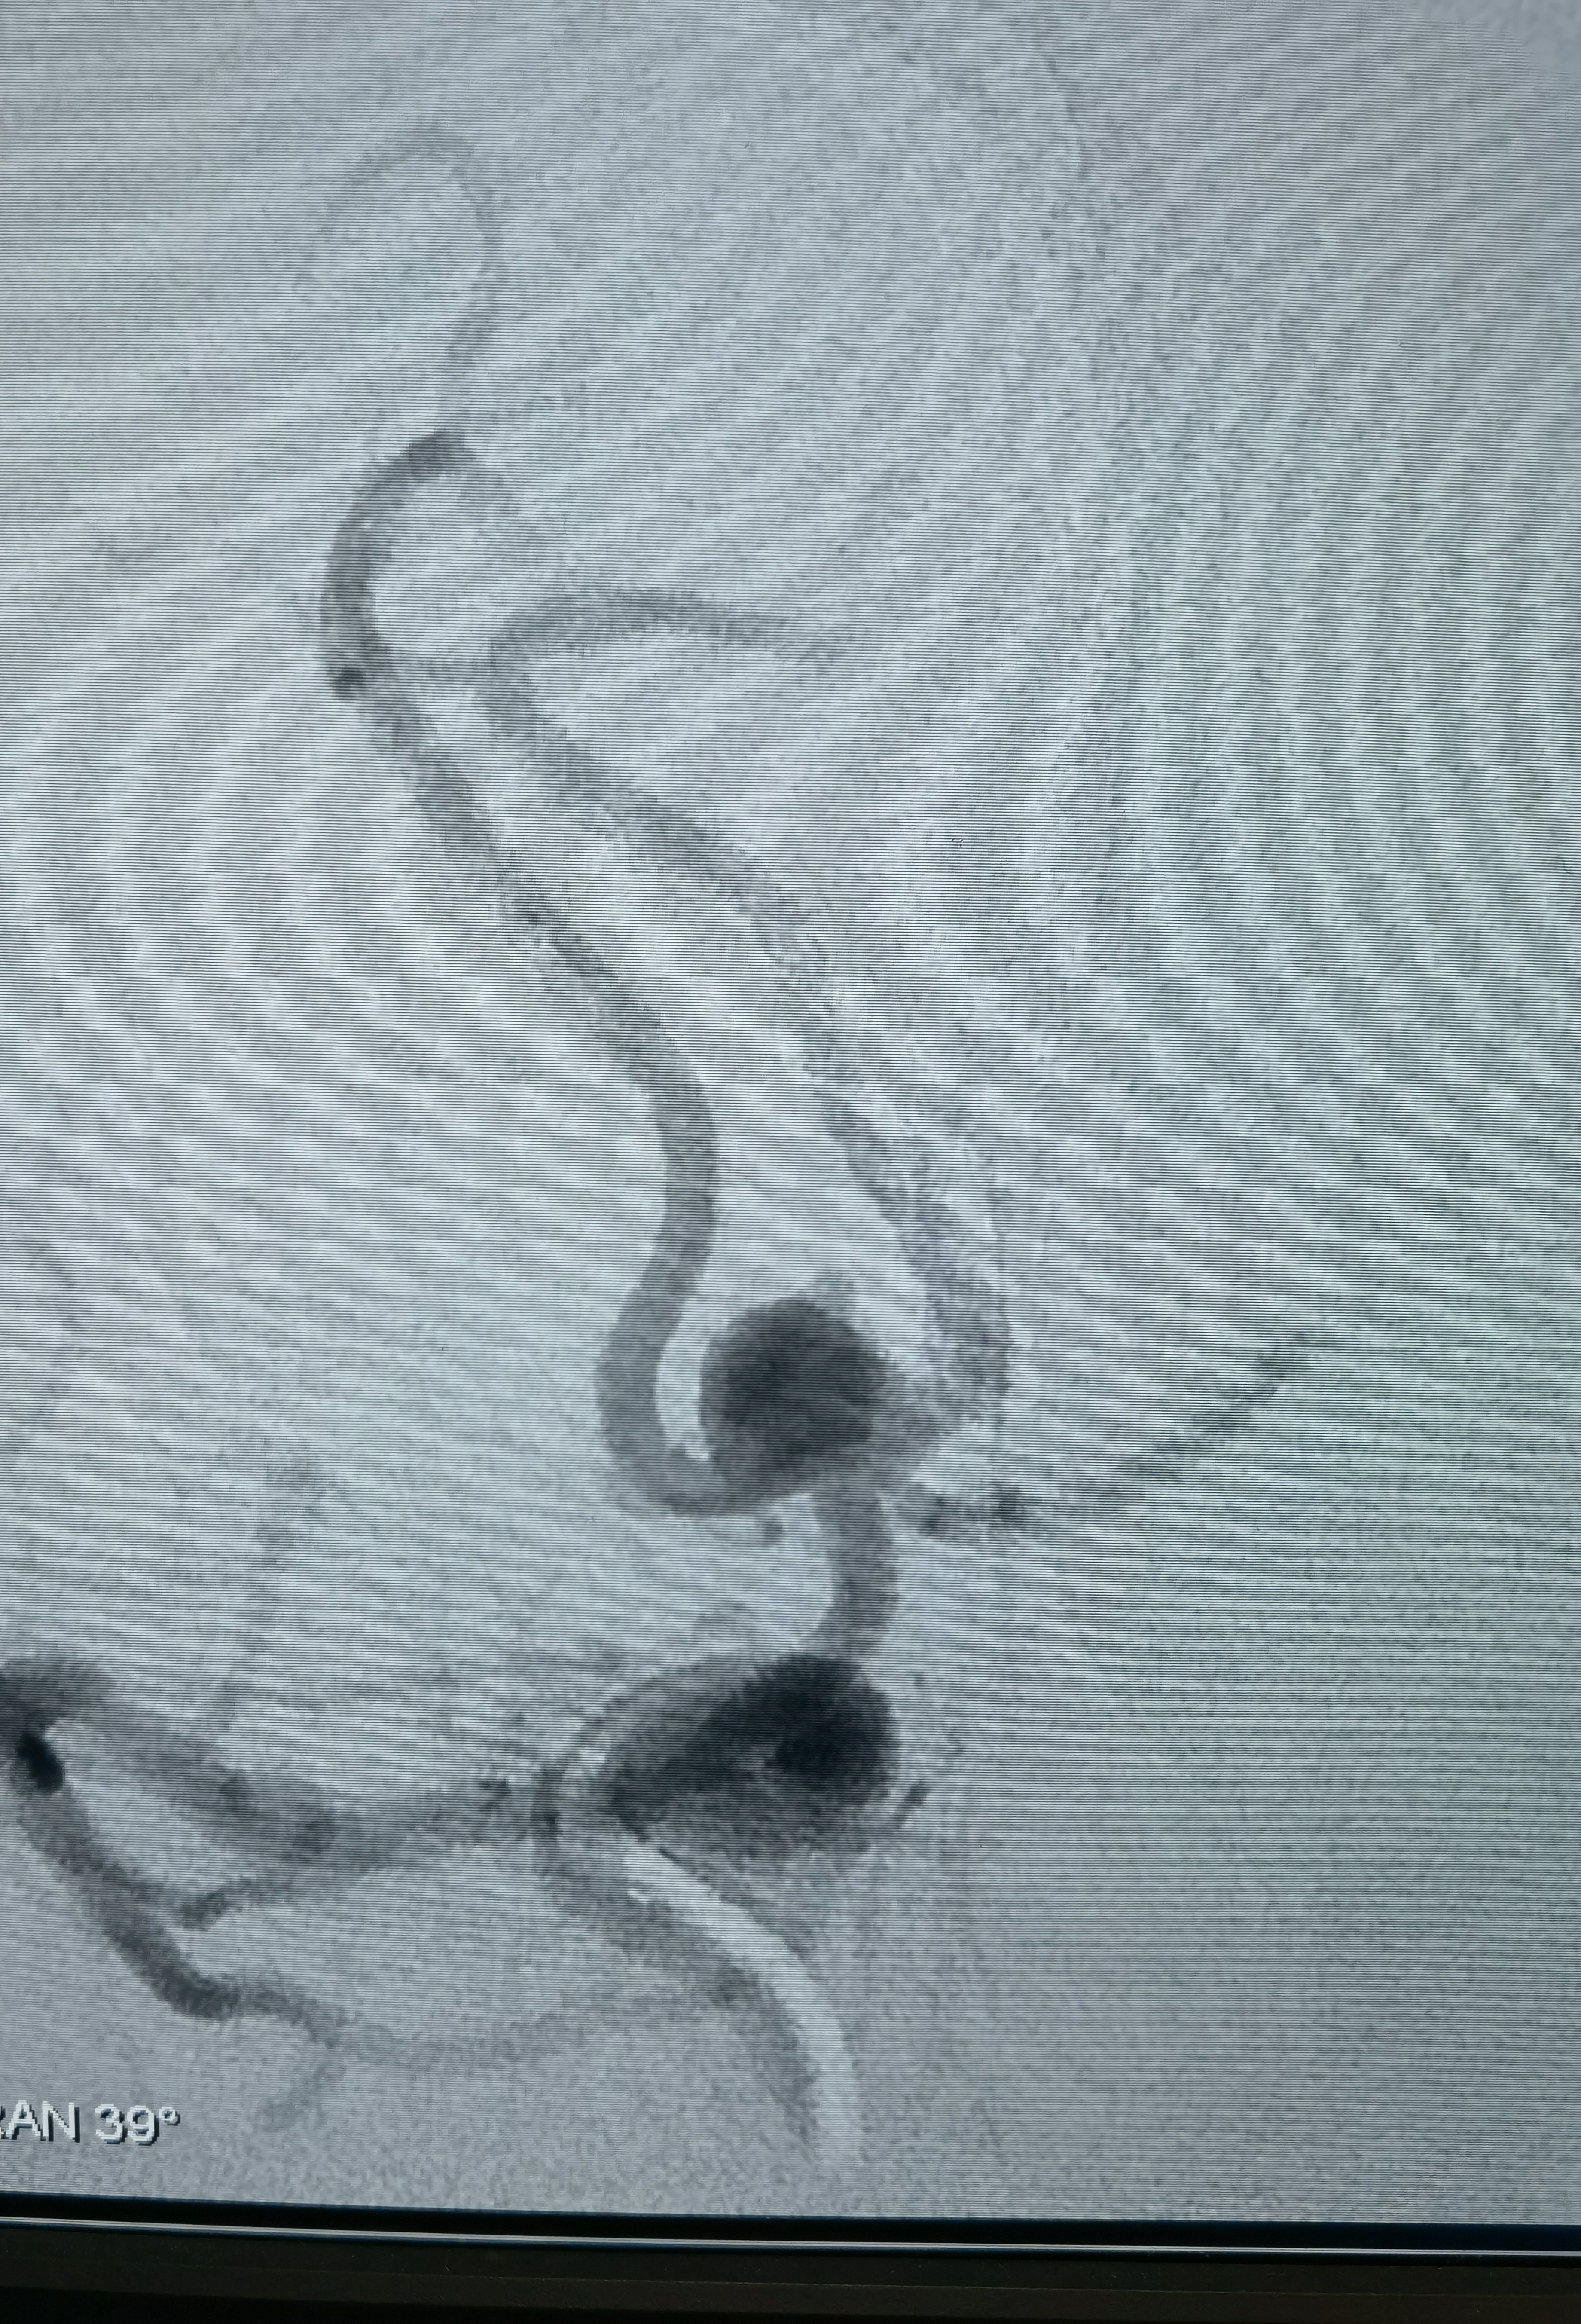

女性,63岁,体检发现动脉瘤,造影显示动脉瘤带子囊,破裂风险大,手术干预!

侧位造影